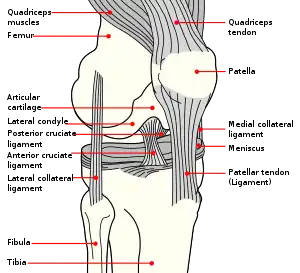

The front and back surfaces are joined by a thin margin and towards centre by a thicker margin.[1] The tendon of the quadriceps femoris muscle attaches to the base of the patella.,[1] with the vastus intermedius muscle attaching to the base itself, and the vastus lateralis and vastus medialis are attached to outer lateral and medial borders of patella respectively.

The primary functional role of the patella is knee extension. The patella increases the leverage that the quadriceps tendon can exert on the femur by increasing the angle at which it acts.

The patella is attached to the tendon of the quadriceps femoris muscle, which contracts to extend/straighten the knee. The patella is stabilized by the insertion of the horizontal fibres of vastus medialis and by the prominence of the lateral femoral condyle, which discourages lateral dislocation during flexion. The retinacular fibres of the patella also stabilize it during exercise.